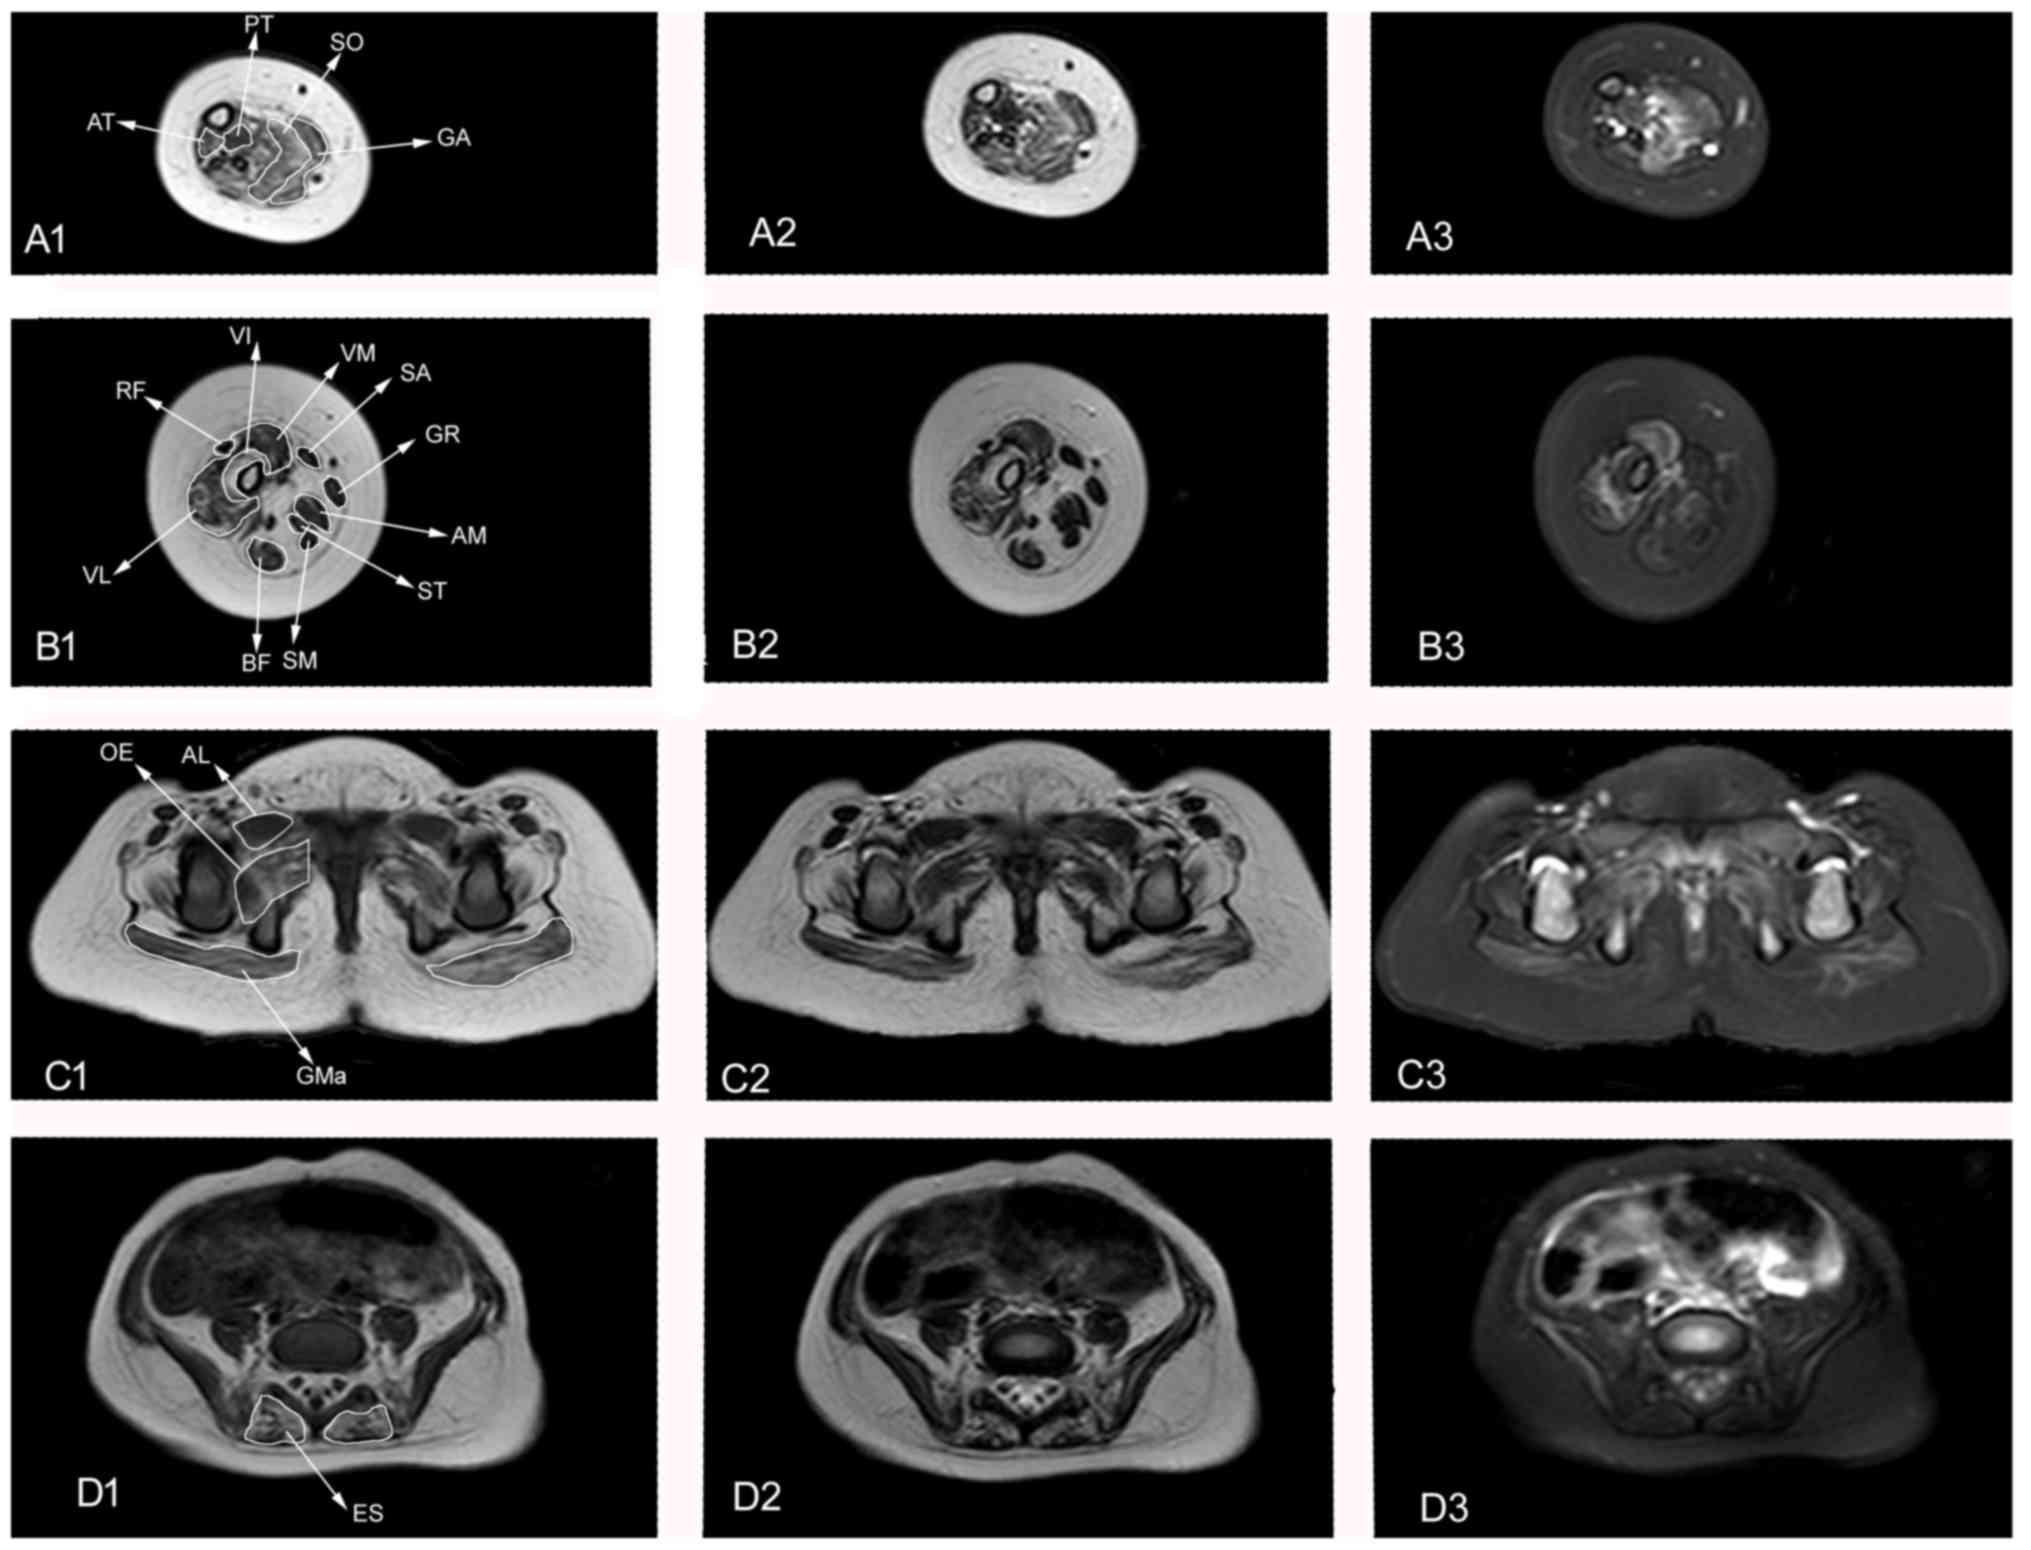

Muscle MRI findings in a one-year-old girl with merosin-deficient congenital muscular dystrophy type 1A due to LAMA2 mutation: A case report

The objective of the present study was to characterize the muscle magnetic resonance imaging (MRI) features of a 1-year-old girl with merosin-deficient congenital muscular dystrophy type 1A (MDC1A). Beginning as an infant, this patient exhibited severe hypotonia and proximal weakness, as well as delays in developmental milestones. Her serum creatine kinase levels at 3 months, 8 months and 1 year were 2,959, 1,621 and 1,659 U/l, respectively. Brain MRI indicated symmetric, mild T1WI low, mild T2WI and FLAIR high radial patterns in the white matter of the Cornu posterius of the ventricular lateral. Gene sequencing demonstrated a heterozygous frame-shift mutation in the LAMA2 gene, consisting of an AG deletion at nucleotides 2049-2050 (LAMA2 c.2049_2050delAG). Lower limb muscle MRI presented obvious fatty infiltration of the muscles and muscle atrophy during the early stage of the disease. The gluteus maximus, erector spinae, vastus intermedius, vastus lateralis, adductor magnus, soleus and gastrocnemius muscles were involved, whereas the piriformis, obturator internus, pectineus, adductor longus, adductor brevis and sartorius muscles presented mild or no involvement. Fatty infiltration of the erector spinae was observed during the early stage of the disease. As an additional tool in the differential diagnosis of muscle disorders, muscle MRI can delay the need for muscle biopsy.